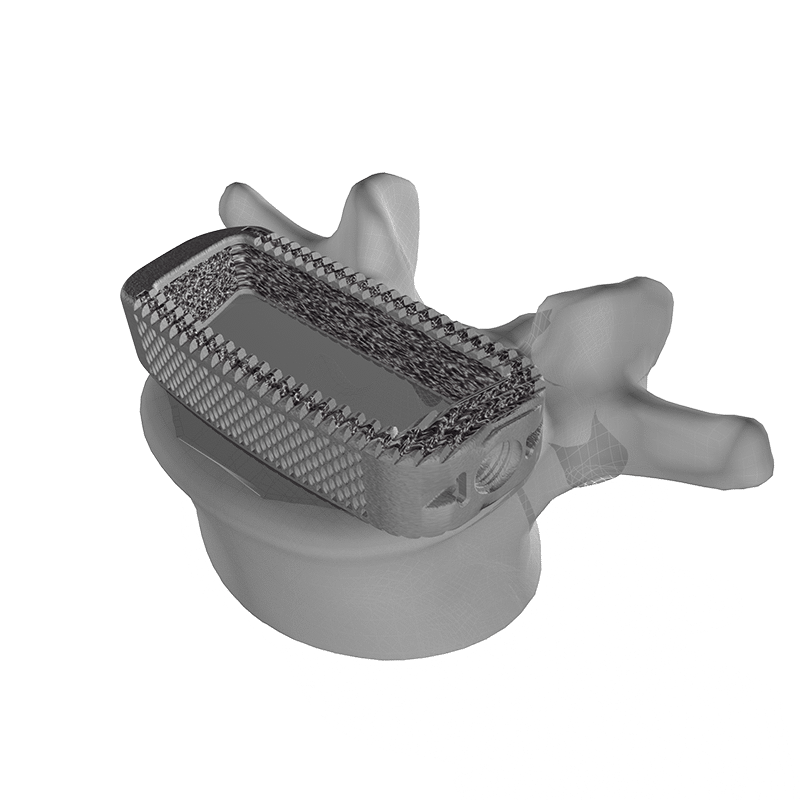

F3D Lateral Interbody

The F3D Lateral interbodies leverage the benefits of Mimetic Metal® technology which emulates key characteristics of natural bone to provide an optimal structure and environment for healing.

Product Features

- Optionally attach to the Oro™ Lateral Plate

- Unique trapezoidal geometry for precise anatomical fit

- 100% open-pore architecture

- Provided sterile via irradiation